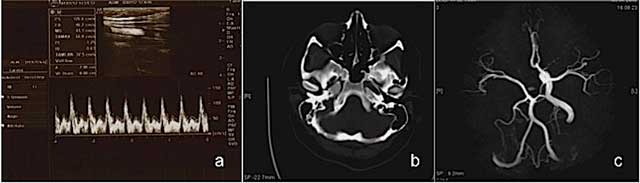

A 19-year-old female patient with a few days history of severe headache, dizziness, nausea, vomiting and syncope was admitted for cranial CT examination. Her physical and neurological examinations were normal and her medical history was unremarkable. The color Doppler sonography revealed absence of the right ICA and a changing flow pattern of common carotid artery, from a low peripheral resistance pattern proximally into a high peripheral resistance pattern similar to that seen in the external carotid artery distally (Figure 1a). The brain CT showed absent right ICA and bony carotid canal without any intraparanchymal pathology (Figure 1b). MRI and MR angiography findings showed right ICA agenesis and as well as anomalous origin of the ophthalmic artery derived from right middle cerebral artery (MCA). The aortic arch and major aortic branches were normal (Figure 1c).

Figure 1

Ultrasound and Color Doppler images reveal right ICA agenesis and externalization flow pattern of right CCA (a); an axial CT image at bone window reveals absent right bony carotid canal (b); MR angiography image shows right ICA agenesis and anomalous origin of ophthalmic artery (c) in Case 1.